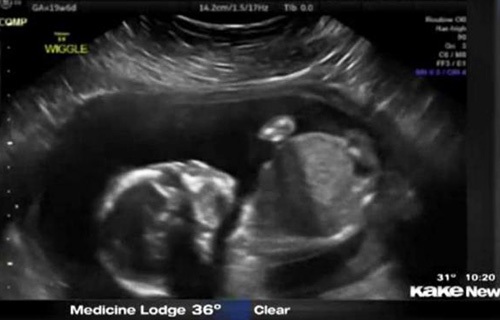

子宫内胎儿自打脸

还只有5个月半的胎儿 居然自己打自己的脸,这也太奇葩了,将来可能是个拳王啊。~美国堪萨斯州一个5个月半大的胎儿在母亲子宫内打自己的脸并把自己击倒,这一幕刚好被父母用超声波检测仪记录了下来,并被分享到网上,引得众人称奇。

这对夫妇原本还担心儿子可能会有脑震荡,但护士让他们放心。凡妮莎说,这次的事件导致他们开始考虑儿子的个性:“我们俩都爱终极格斗。所以我们正在讨论他或许会成为一个拳击手?!?/span>